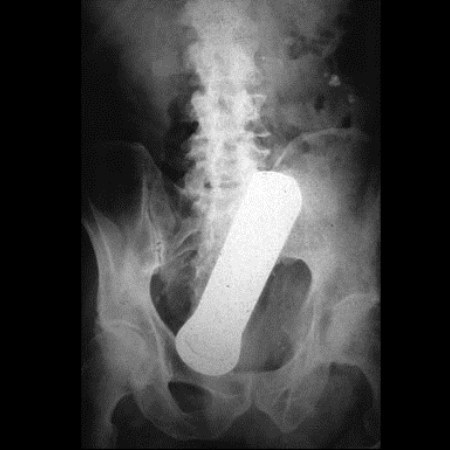

2. Uma lanterna